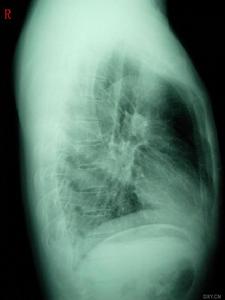

檢查

職業性哮喘對哮喘者進行職業性病因評價十分重要。判斷病因需要依靠各項指標的綜合分析,目前已被世界各國公認的指標是:

2.肺功能實驗

3.最大呼氣流速(PEF)的監測